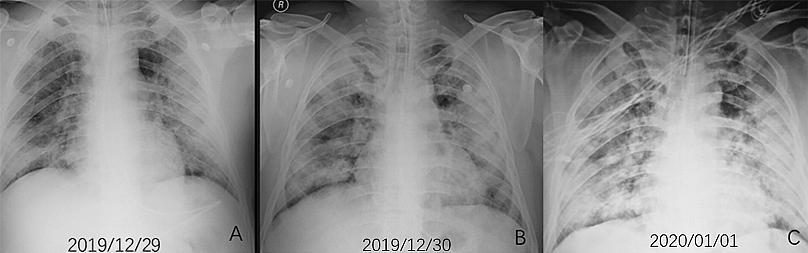

Koronavirüsün kaynağı olduğu düşünülen Vuhan kentindeki balık pazarında ulaşım görevlisi olan 44 yaşındaki bir erkeğin röntgen (X-ray) görüntülerindeki "opasifikasyon (buzlu cam görünümleri)" denilen beyaz lekeler, hastada oluşan zatürrenin boyutunu resmediyor.

Akut solunum sıkıntısı sendromu ve ileri derece zatürre teşhisi konulan hasta, 13 gün süren yüksek ateş ve öksürük şikayeti üzerine hastaneye başvurduktan bir hafta sonra hayatını kaybetti. Söz konusu hasta şüpheli Covid-19 vakası olarak tanımlanıyordu.